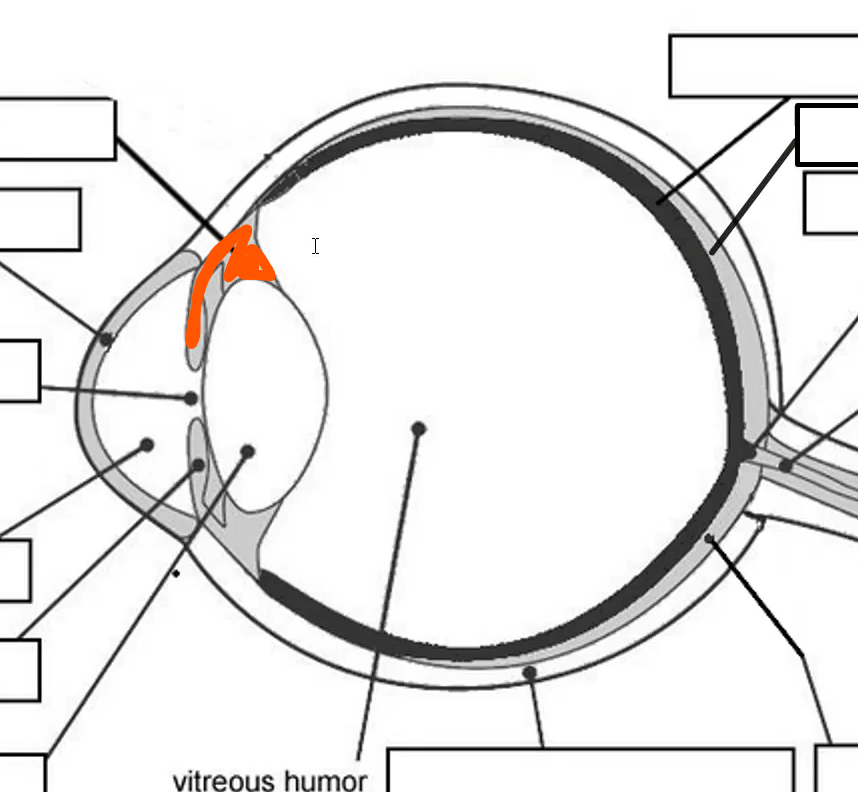

Name

cornea

allows light, most sensitive part of body

Name

Ciliary body

controls shape of lens

Name

Choroid

Name

Tapetum

Name

Optic nerve

Orange name

Retina

Orange

Iris

Blue

Pupil/lens

Red

Lens

Blue

Retina

Green

vitreous humor

Gray

Iris

Green

Sclera

Blue

Pupil

Orange

Anterior compartment

Maintains pressure